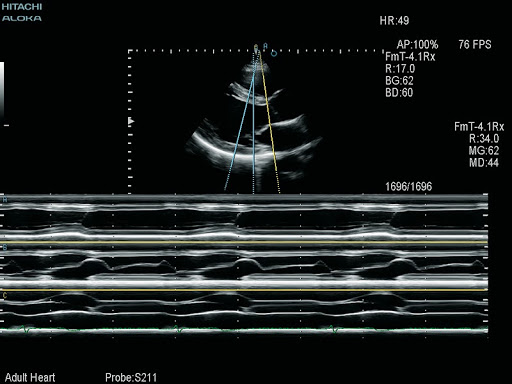

- FmT, WbT и HdTH тканевые гармоники трёх поколений

- Цветной и тканевой М-режим

S211 – Секторный фазированный датчик для проведения эхокардиографических исследований взрослых.